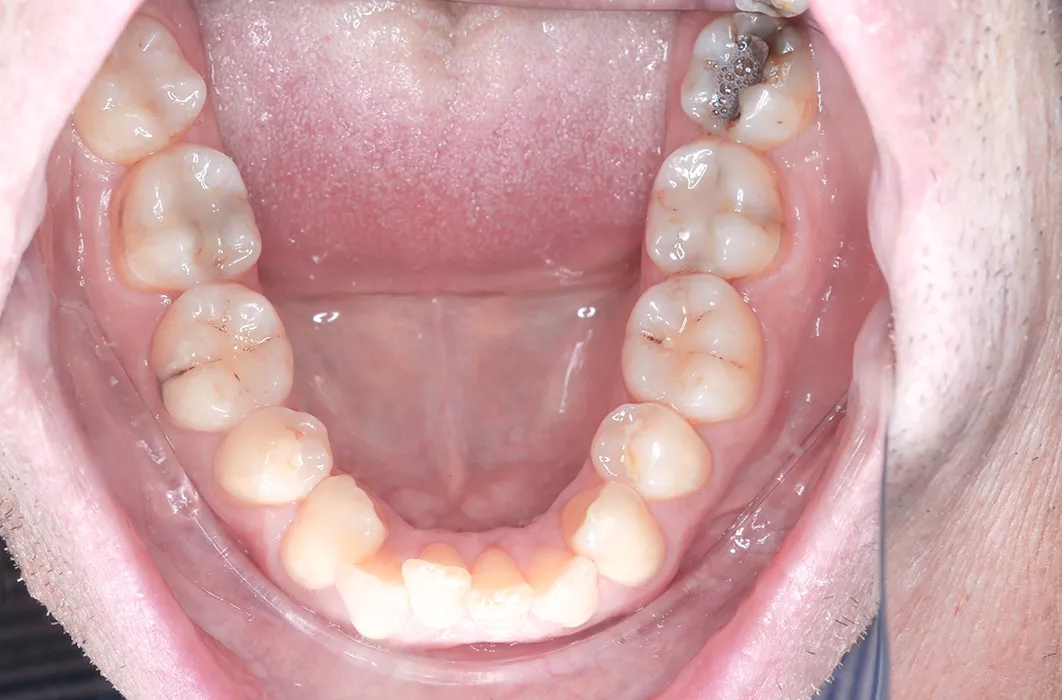

At Simply Teeth, our focus is on preserving and protecting your natural teeth. Dr Jennifer recently treated Mr C, a patient whose back teeth showed significant wear, decay, and older amalgam (silver) fillings that had started to darken and break down. These findings indicated a risk of further structural breakdown if left unmanaged.

On his first visit, Mr C’s back teeth showed:

- Plaque buildup and staining across multiple areas.

- Visible tooth wear and cavities, especially on the molars.

- Severe decay on his upper left molar (tooth 27) and lower left molar (tooth 38).

- Old amalgam fillings that had discoloured and were no longer providing full protection.

The condition of the teeth made intervention necessary to maintain stability and function.